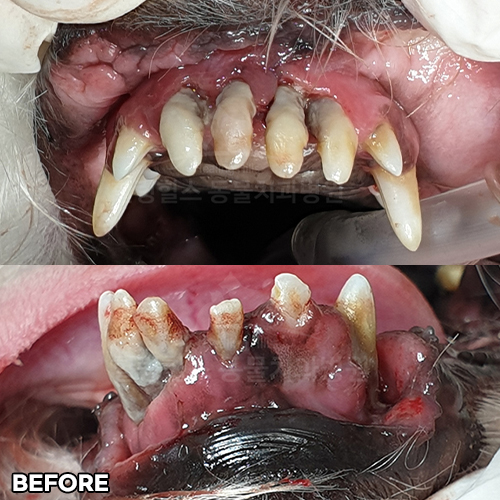

[심한 치주염 최대한 치아를 살리며 최소침습적발치]

샘플